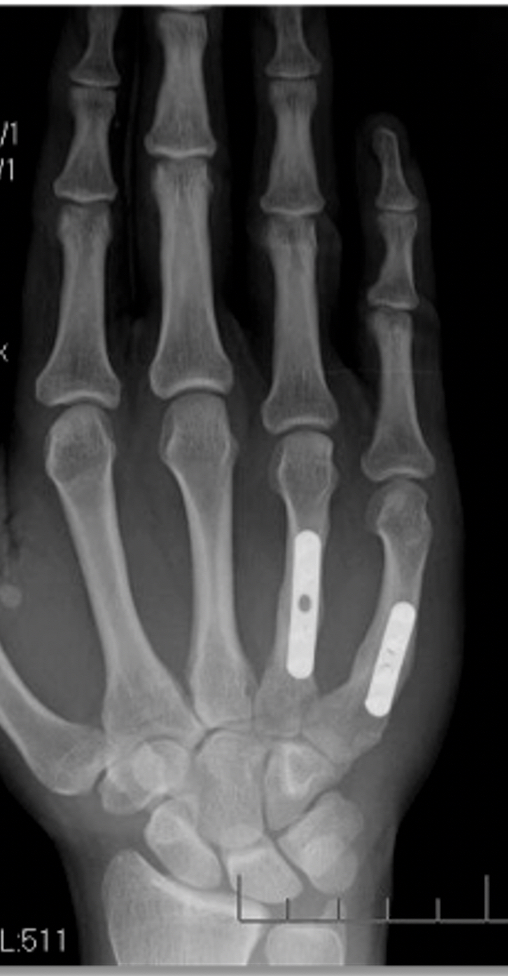

Surgery – Surgery may be recommended again where the injury is unstable. There are a number of different techniques used by surgeons including putting wires into the bone. Generally speaking, the preferred method of treatment in Fife is to use a bone plate.